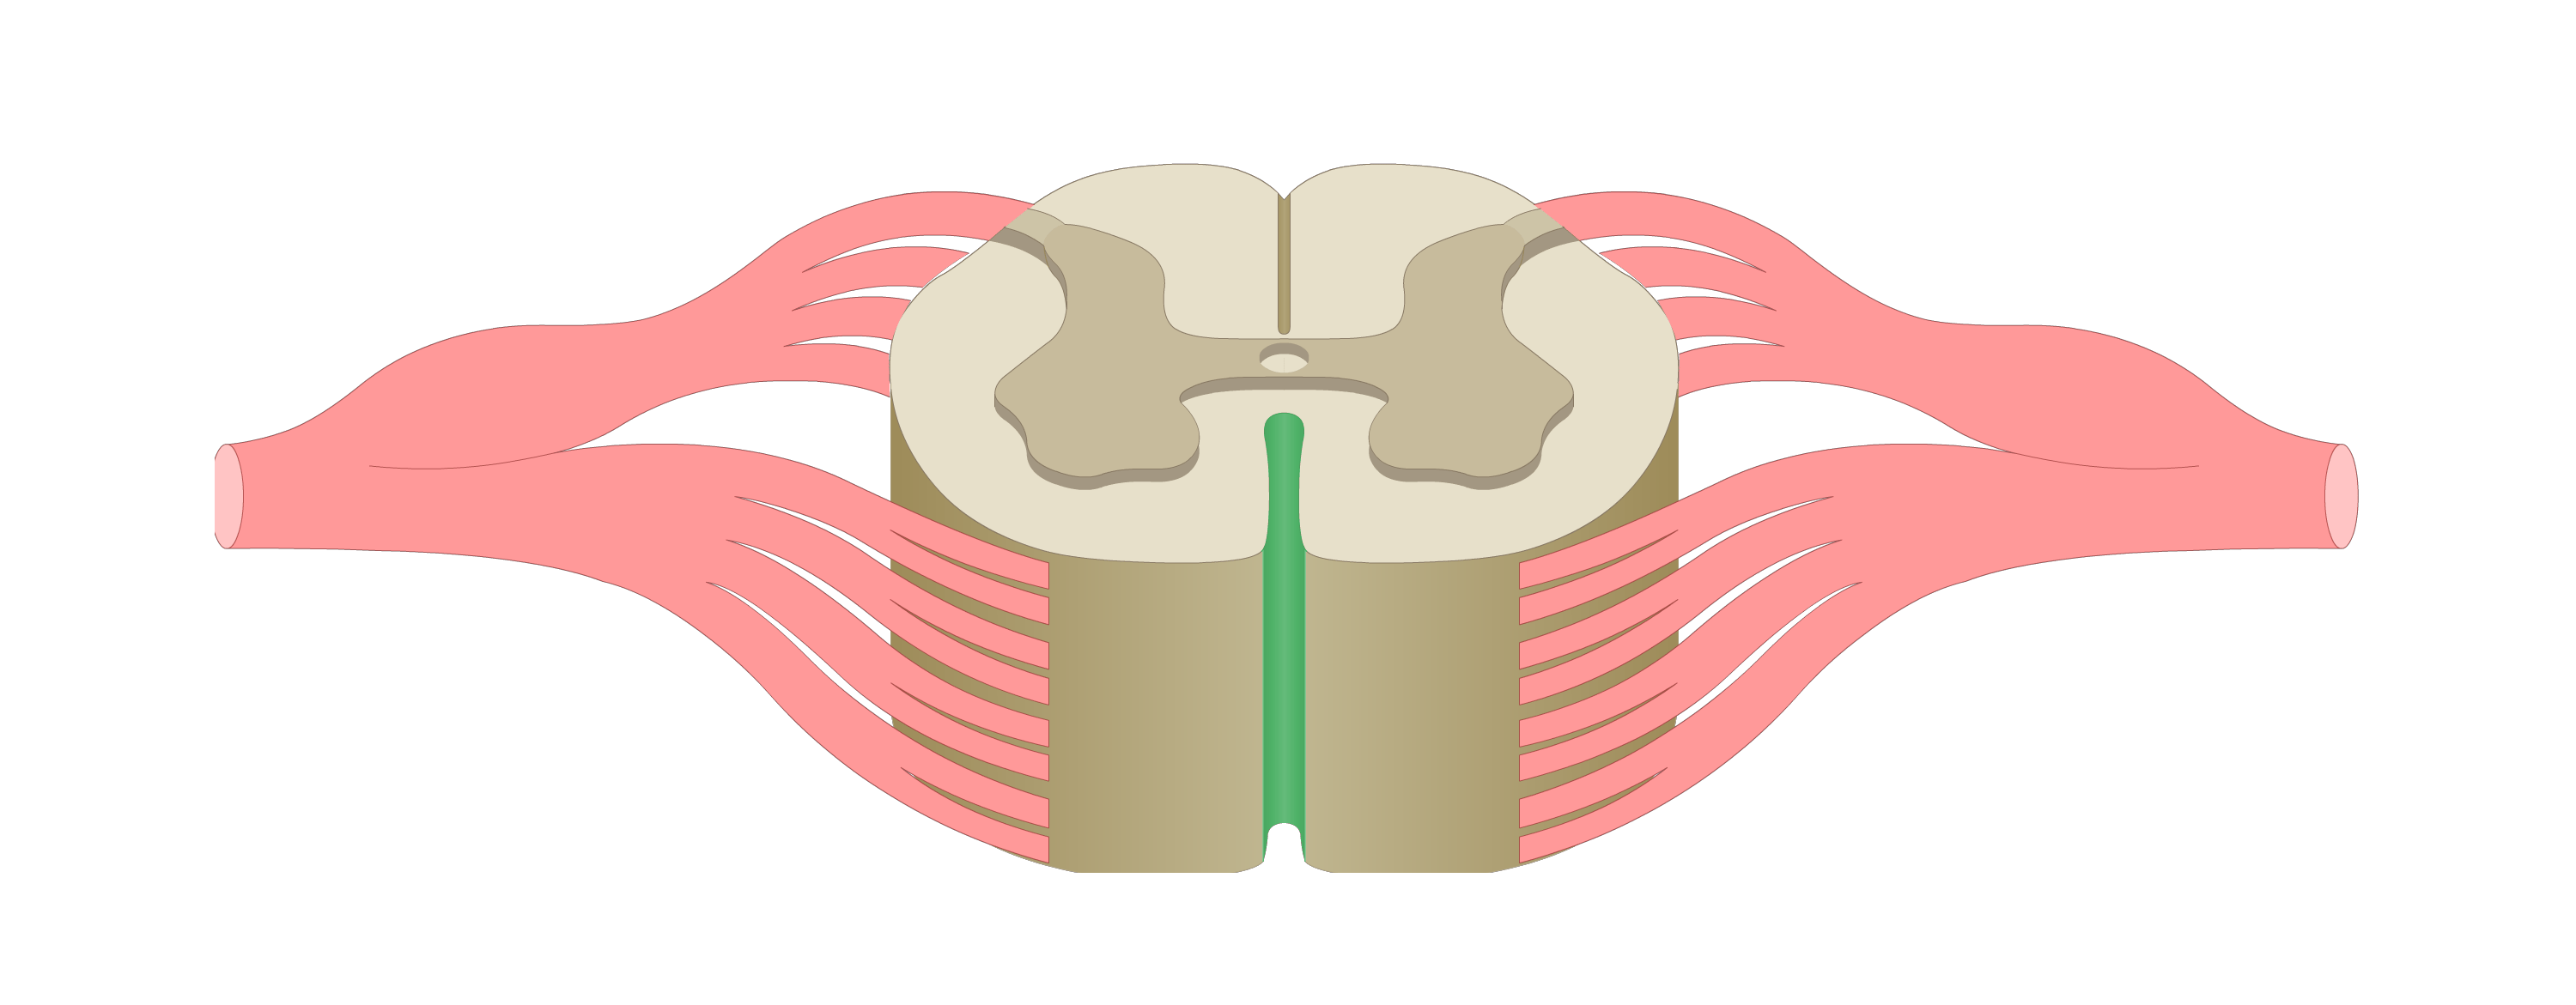

motor tracts

sensory tracts

dorsal root ganglion

dorsal horn

lateral horn

ventral horn

dorsal funiculus

lateral funiculus

ventral funiculus

central canal

ventral median fissure

dorsal median sulcus